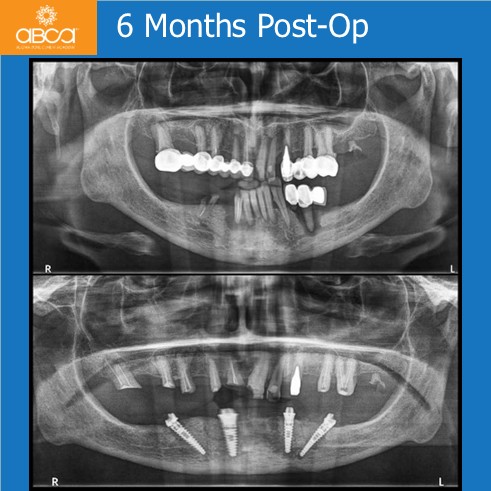

The patient presented with a severe bone defect involving the inferior alveolar canal and mental foramen, with limited bone height and high risk of nerve injury. Using Augma Bond Apatite® to fill in the defects, restore bone volume and enhance implant stability. At six months, new bone fully integrated around stable implants, providing strong biological and mechanical support. After eight years, bone volume remained preserved with no significant resorption, confirming Augma’s long-term success in transforming a high-risk defect into a predictable, stable rehabilitation.